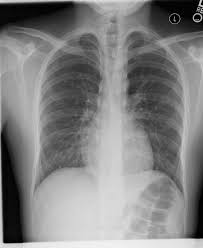

This lung infection produces coughing, fever, shortness of breath, and chest pain. Bacterial pneumonia is characterized by exudative solidification (consolidation) of the pulmonary tissue, which is caused by bacterial invasion of the lung parenchyma. Learn about causes, risk factors, prevention, signs and symptoms. Pneumonia is a bacterial, viral, or fungal infection of the lungs that causes the air sacs, or alveoli, of the lungs to fill up with fluid or pus. Pneumonia por pneumocystis jirovecii 4.

Abcesso pulmonar (temos observado muitos casos de abcessos. A pneumonia eosinoffii~a aguda (pea) e uma doe~ rara, de etiologia desconhecida, caracterizada por eosinofilia pulmonar marcada, geralmente niio associada a aumento dos eosinofilos no sangue. Bacterial pneumonia is an infection of your lungs caused by certain bacteria. Bacterial pneumonia is a type of pneumonia caused by bacterial infection. When pneumonia is caused by streptococcus pneumoniae, mycoplasma pneumoniae, or other bacteria, it's called bacterial pneumonia. Pneumonia poate fi cauzată și de inhalarea secrețiilor de vomă sau a unor substanțe. Clinical presentation bacterial pneumonia has symptoms similar to other pneumonia. Bacterial pneumonia is characterized by exudative solidification (consolidation) of the pulmonary tissue, which is caused by bacterial invasion of the lung parenchyma. Histologic features and clinical significance. This lung infection produces coughing, fever, shortness of breath, and chest pain. Learn about bacterial pneumonia causes, symptoms, the contagious period, treatments, and recovery time. Pneumonia can be generally defined as an infection of the lung parenchyma, in which consolidation of the sections bacterial pneumonia. Streptococcus pneumoniae (j13) is the most common bacterial cause of pneumonia in all age groups except.